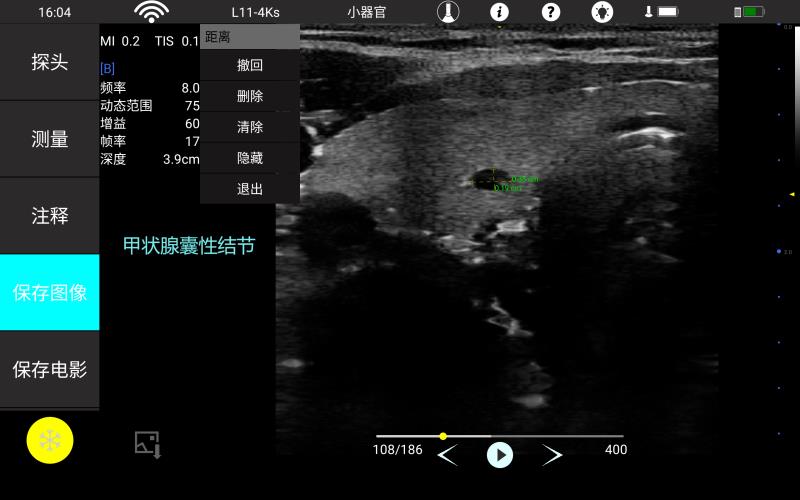

• 线阵

甲状腺

多种专科软件包,含常规测量,腹部,产科,

妇科 心脏,小器官,神经应用软件包,使检查更便捷。